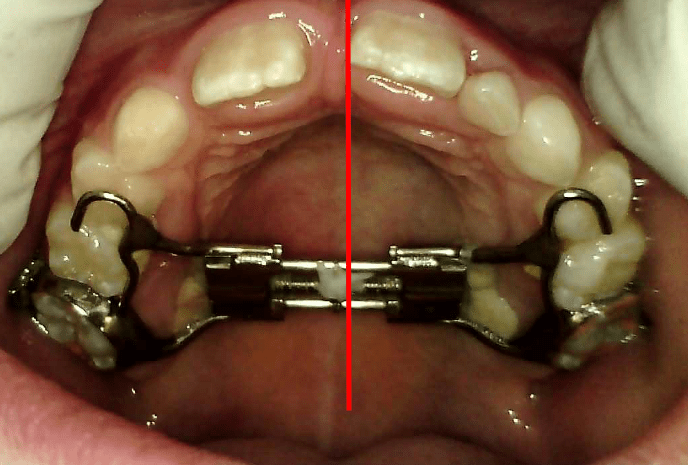

EARLY INTERVENTION

Early Orthodontic Solutions: RME and Myobrace Appliances Modern orthodontic treatment offers a range of tools designed to guide healthy dental development in children. Two key appliances—Rapid Maxillary Expansion (RME) and Myobrace—play vital roles in early orthodontic care by addressing jaw development and oral habits. Here’s a look at what each does and how they help… Read.